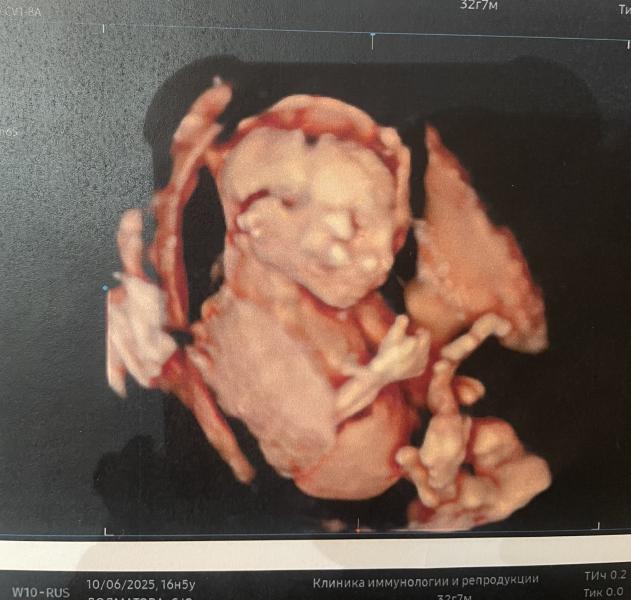

16 недель беременности: как справляюсь с антителами

С опозданием. Наши 16 недель 👍🏻 антитела утихли и в метипреде отказано, спасаемся плаквенилом. Продолжаем расти. 17 недель первые шевеления 🥰